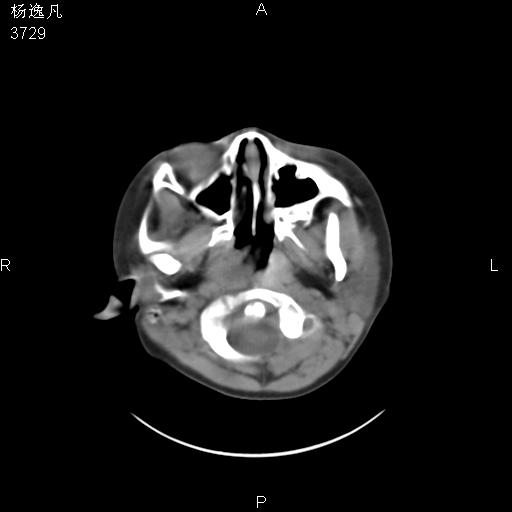

男性,5岁,面部受外伤,余无特殊

软组织窗

鼻咽顶后变窄。顶后壁增厚,考虑腺样体肥大。其它未异常/

1、右面部及颞部软组织肿胀。

2、腺样体肥大。

头颅ct平扫未见明确外伤性征象,右侧面部及颞部软组织肿胀,后鼻腔软组织影增大,增厚,鼻咽顶部变窄,考虑鼻咽腺样体增值肥厚。